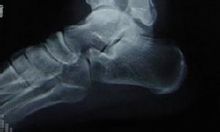

全身各部位的肌肉、韌帶、筋膜、腱鞘、滑膜的急慢性損傷或退行性變,骨關節病亦適用。

骨刺的封閉療法壓痛點封閉 適用於單純軟組織急慢性勞損,肌肉附著點痛及筋膜痛等。